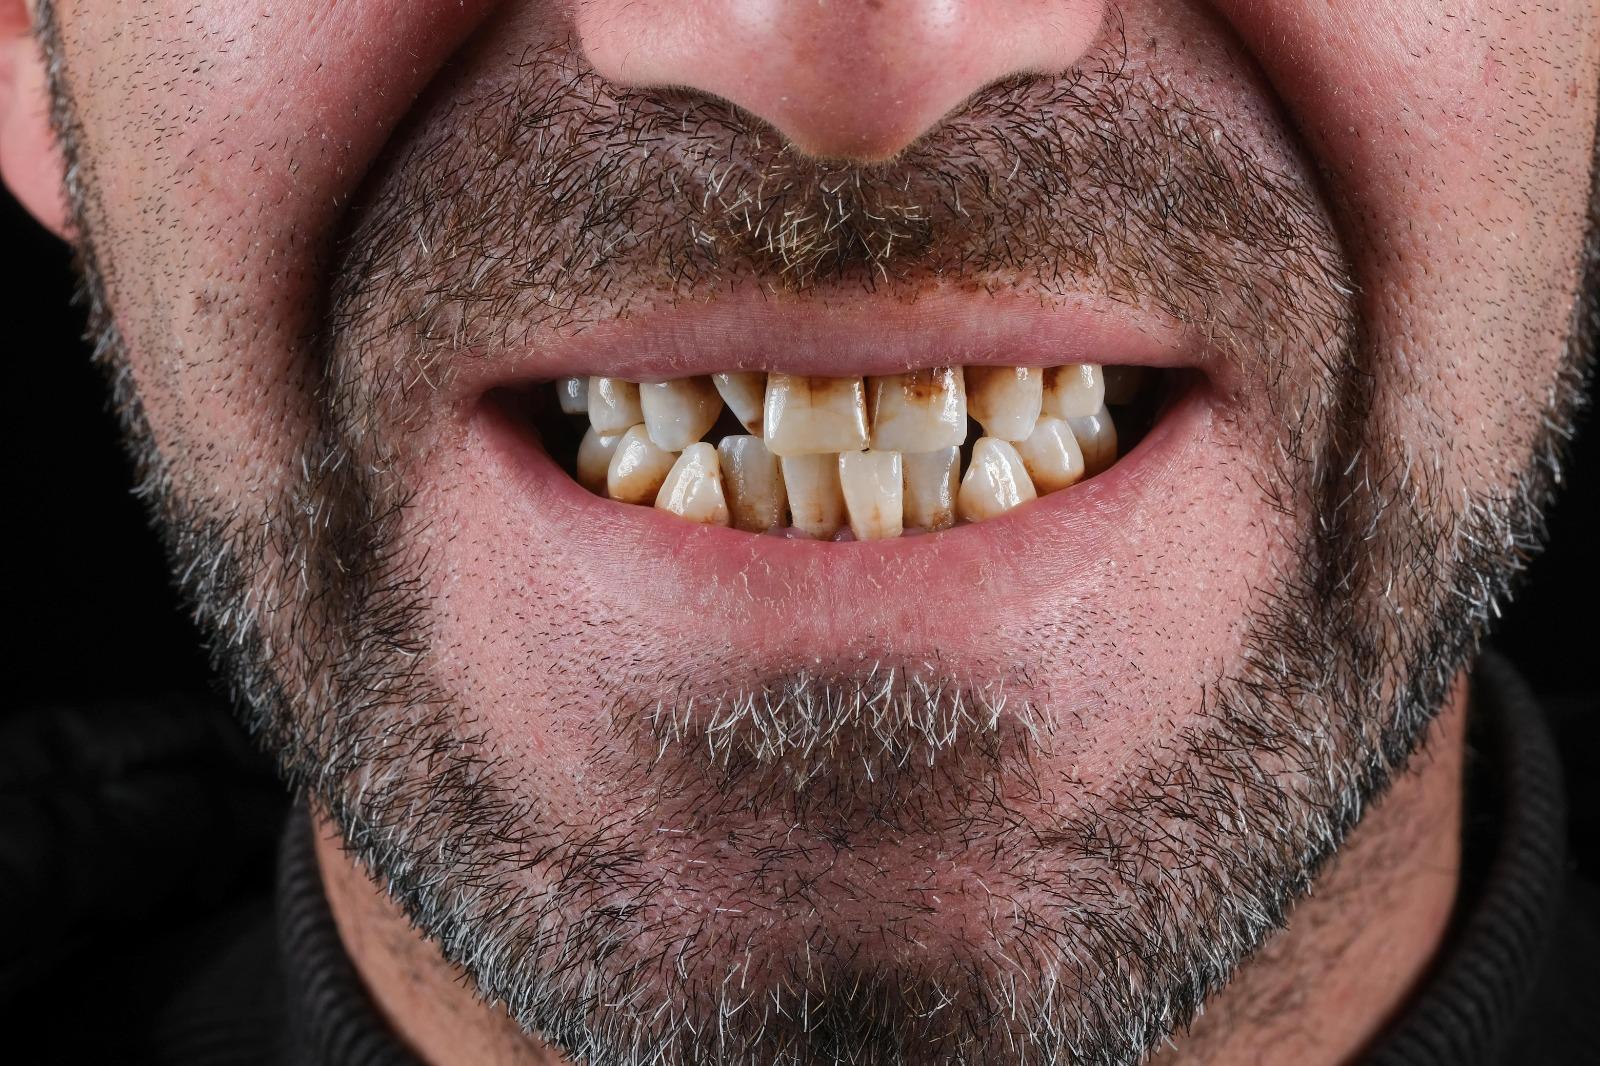

All-On-Four

The All-on-Four treatment is a comprehensive implant rehabilitation method applied in individuals who have lost all their teeth or whose existing teeth can no longer function properly. This technique is based on placing four implants into the jawbone at specific angles and constructing a fixed prosthesis on top of these implants. Angled placement of the posterior implants allows treatment even in cases with limited bone volume. The process begins with a detailed clinical and radiological evaluation. The patient's general health condition, jawbone density, and oral structure are analyzed to create a personalized treatment plan. In suitable cases, a temporary fixed prosthesis can be placed on the same day, helping the patient adapt more comfortably to the treatment period. Permanent prostheses are prepared after the healing process is completed. This method is a comprehensive solution that restores aesthetics, speech, and chewing functions.